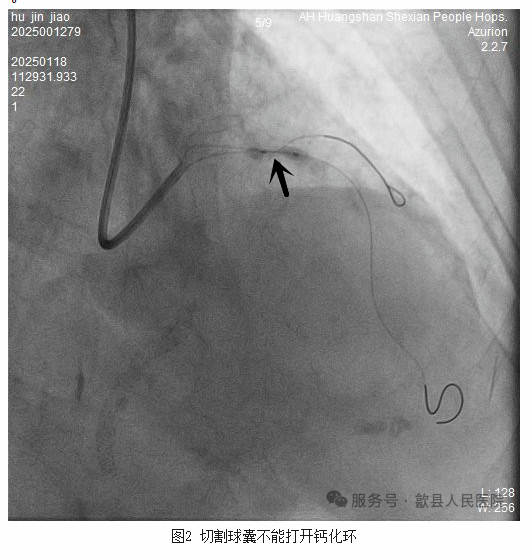

俞志雄副主任医师团队成员方勇医师快速将导丝通过病变,但和他预料的一样,2.5mm的非顺应性球囊无法通过,当机立断便采用延长导管辅助下艰难的将2.5mm非顺应性球囊通过病变,但20个大气压仍然不能将病变充分扩开,随后改变策略,使用2.5mm切割球囊常规10个大气压仍然不能将病变处的钙化环打开(图2)。